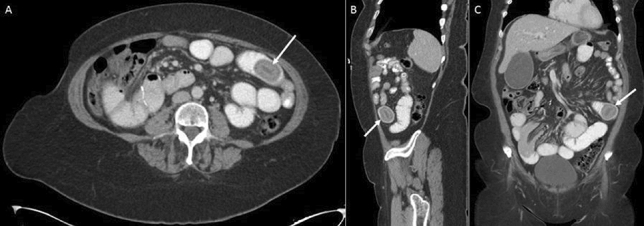

Methods and Procedures: Twenty-four patients underwent abdominal wall reconstruction (AWR) between January 2017 and June 2022 by a single surgeon at our institution. Lifestyle information (smoking, diabetes, and obesity status) and procedure-related metrics (pre-operative botox use, hernia characteristics, and mesh type) were obtained. The ellipsoid formula (V = 4/3ABC) was used to calculate volume of the hernia sac (VIH) and abdominal cavity (VAC) (Fig. 1). Measurements at initial visit and time of surgery were compared and analyzed using a two-tailed T Test (p < 0.05 signified significance).

Results: Pre-operative counseling results are shown in Table 1. Procedure-related metrics are shown in Table 2.

Fig. 1 Hernia sac measurements for calculating VIH (Left to right: axial, sagittal, coronal)